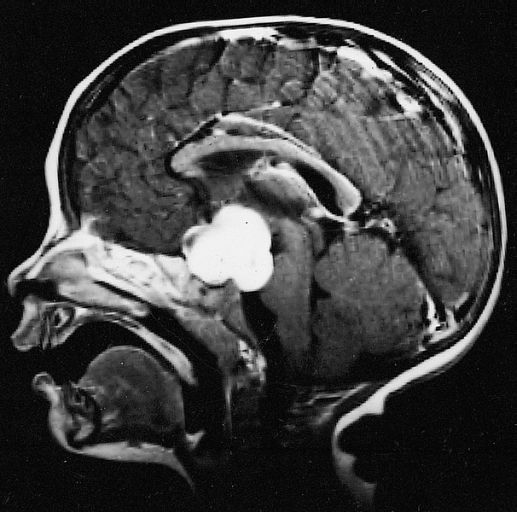

Astrocitomas I

Son gliomas benignos que pueden ser sólidos o sólidos con quistes. Se localizan en el cerebro y en el cerebelo. En el cerebro pueden estar en el hipotálamo y son los más difíciles de extirpar, igual que los localizados en el tronco cerebral, pero en muchos casos se puede realizar extirpaciones completas, también se localizan en los hemisferios cerebrales o cerebelosos siendo la extirpación más sencilla con la ayuda de las modernas técnicas quirúrgicas como son navegadores, microscopio, coagulación bipolar, aspirador ultrasónico, etc.